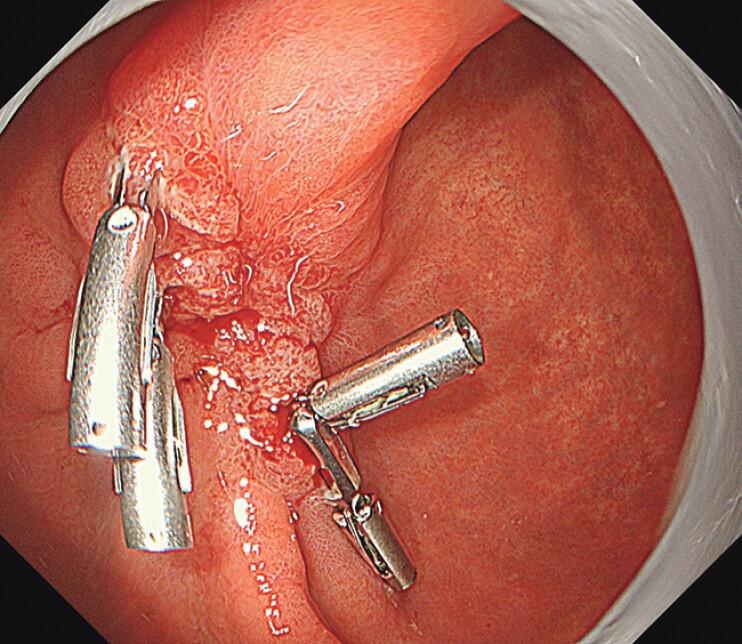

Effective closure of post-gastric endoscopic submucosal dissection defect using anchor-pronged clip, string-clip, and detachable snare.